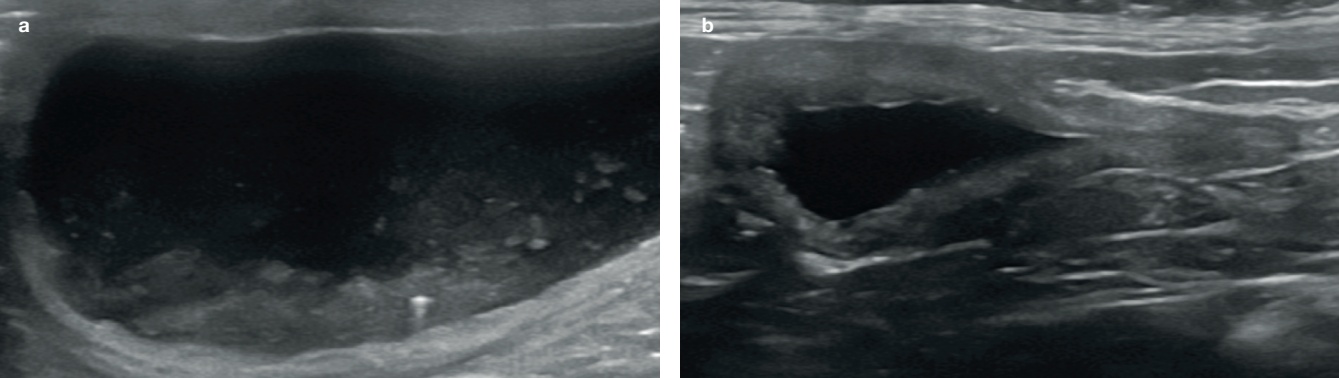

저에코성 혹은 무에코의 수질(medulla)을 확장된 신우로 혼동하지 않는 것이 중요합니다. 신우 확장은 보통 초음파 횡단면(transverse plane)에서 더 쉽게 보입니다. 신우 안의 액체는 심장 모양 또는 초승달 모양의 무에코성 부위로 보이며, 신장 능선(renal crest)을 감싸는 형태를 보입니다(그림 1).

신장을 배 측면(dorsal plane)으로 보면 신우 확장은 선형~타원형으로 보입니다. 확장이 점점 심해지면 신우는 둥근 모양을 나타냅니다(그림 2).